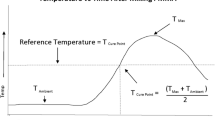

A thermal imaging camera (FLIR systems, West Malling, England) was placed 1 m from the anterior cortex and centred over the position of the cement bolus. Images were taken every 20 s. The emissivity value was set to 0.99 [12] (Fig. 4).

For the samples with no fracture, the correlation between the temperatures recorded by the thermal camera and the thermocouples on the near cortex (thermocouples 1–4) was very strong (r > 0.8) in all but two thermocouple recordings (r = 0.61 and r = 0.53). The correlation between the readings for samples with a fracture was strong or very strong (r = 0.61–0.99). For thermocouples placed on the far cortex at the site of the radial nerve, the correlation was very strong (r > 0.8) in all but one recording (r = 0.73), for thermocouples elsewhere on the far cortex, the correlation was less strong and as the distance from the centre of the cement bolus increased, became negative in the majority of cases (Table 1).

Given the small absolute differences in the observed temperatures, attention was then turned to the time spent in excess of temperatures that may result in nerve damage. Due to strong correlation between the two measurement modalities, we have opted to use only the thermal camera data to present this. For the data recorded by the thermal camera, five out of nine samples without a fracture with complete data recorded a temperature in excess of 47 °C for more than 1 min compared to four out of nine samples with a fracture [p = 1.00; RR = 1.25 (0.49–3.12)]. When a threshold of 50 °C for more than 30 s was considered, three samples without a fracture exceeded this value compared to two with a fracture [p = 1.00; RR = 1.50 (0.32–6.95)] (see Fig. 6 in Appendix 1 and Fig. 7 in Appendix 2). No samples in either group exceeded a threshold of 55 °C. When the far cortex thermocouple data were considered (thermocouples 5–8), no samples exceeded 47 °C.

The results demonstrate the elevated temperatures that surrounding tissues are subjected to during the cementing process. Temperatures achieved at the site of the overlying radial nerve were well above body temperature. In five out of nine samples without a fracture and four out of nine samples with a fracture the thermal camera recorded temperatures exceeding 47 °C for over 1 min. The maximum temperatures demonstrated by thermocouple 5, the hypothetical position of the radial nerve, were reassuring overall.